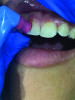

(8.) Dissolvable whitening strips are a desirable option for use as a patient motivator and adjunctive therapy.

Figure 8

The patient plays a vital role in periodontal disease prevention and management. Therefore, the clinician must allot sufficient time to oral health education during each appointment to ensure that patients have the knowledge they need to function as an effective co-therapist for their oral healthcare needs. It can be difficult to keep patients motivated to perform their home care routines. However, patients who whiten their teeth have been found to be more compliant with treatment plans and regularly scheduled appointments. Approximately $1.4 billion is spent each year on over-the-counter whitening products, but patients should be getting whitening recommendations from their providers. Clinicians can help patients stay motivated to maintain their oral health by recommending the use of whitening strips embedded with hydrogen peroxide. Patients then get the benefit of a white smile and the therapeutic benefit from the antimicrobial effect as a result of the oxygenating action of the hydrogen peroxide. Recommended products are formulated with 10% hydrogen peroxide, which is one of the highest over-the-counter percentages available to consumers. The strips are also dissolvable within just 15 minutes, making them a desirable option for use as a patient motivator and adjunctive therapy (Figure 8 through Figure 10). Examples include LumiSmile® White Dissolving Strips (Oral ProCare) and ACCLEAN Professional Dissolvable Teeth Whitening Strips (Henry Schein), for example.